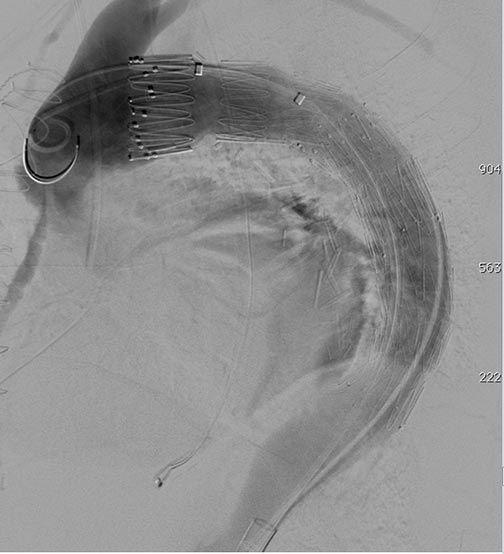

Chapter 9 Fluoroscopy And Angiographic Imaging In Thoracic ...

80 9 Fluoroscopy and Angiographic Imaging Fig. 9.1 (a, b) Illustration with an intra-operative angiogram demonstrating a bovine aortic arch with the innominate and left common carotid artery originating from a common ostium ... View Full Source